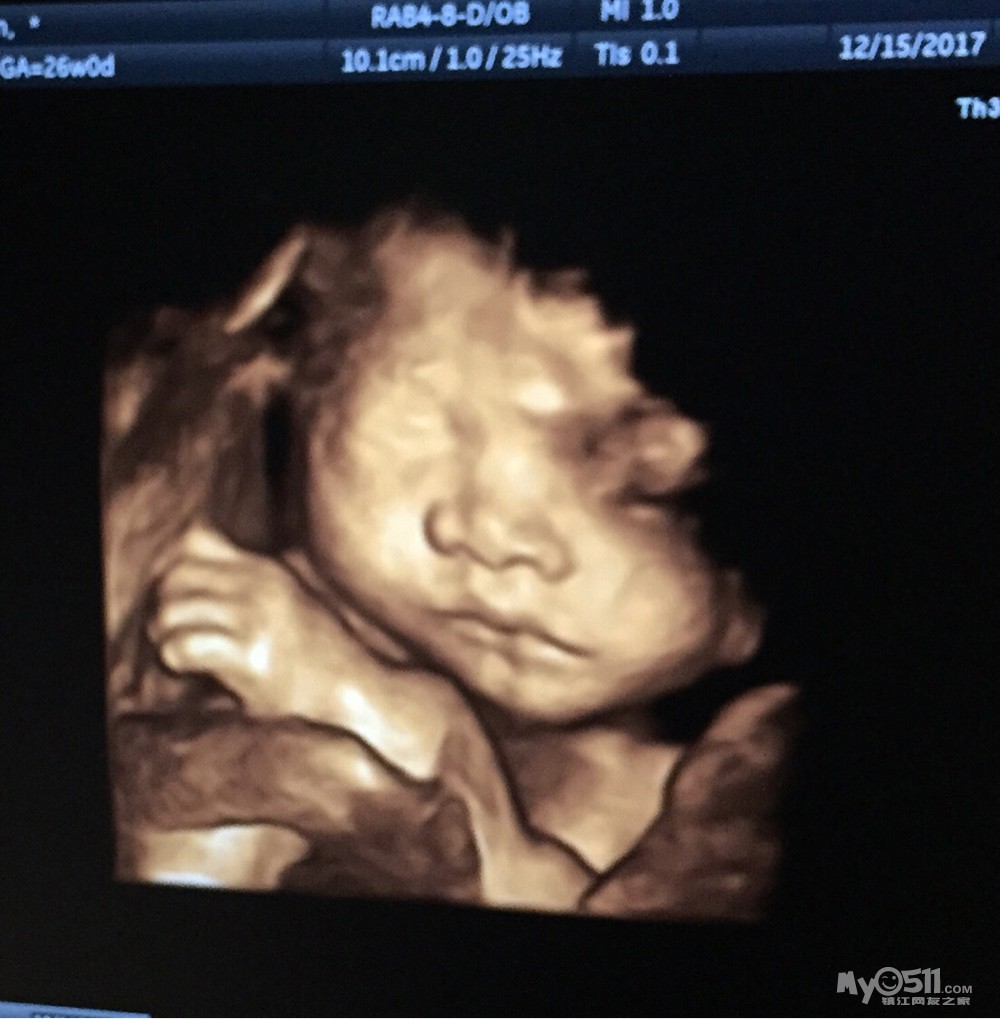

12月11日,去丹阳人民医院做四维的。前几天还梦到四维拍到的宝宝正脸,特别正,特别清晰,长得像个小菩萨似的,又圆又胖。我就期待着顺利通过四维,并且能拍个清楚点的脸,让我看看长得什么样。但是,我家汤圆太不配合了

。我再逛,汤圆爸自己待着玩手机了。我爬楼梯,给汤圆放音乐,吃巧克力。10点再拍,医生都站起来了,过了一会儿说,“气死了,眼看着小脸越来越远,躲到拍不到的地方了。”我真的是没耐心拍了,医生却很有耐心,让我等会儿再拍一次。十点半,再拍,还是拍不到脸,医生说都正常,报告也给我打了。(脸没看到,报告也能说都正常吗?万一脸部有缺陷呢。我的内心是有这个疑问的,没问出来。)中午都来不及吃饭,吃的速冻饺子,下午还上班呢。我还是不甘心啊

。那个医生也好,今天又给我拍了两次呢。附上四维大脸照,可胖了,脸上肉都鼓起来了。